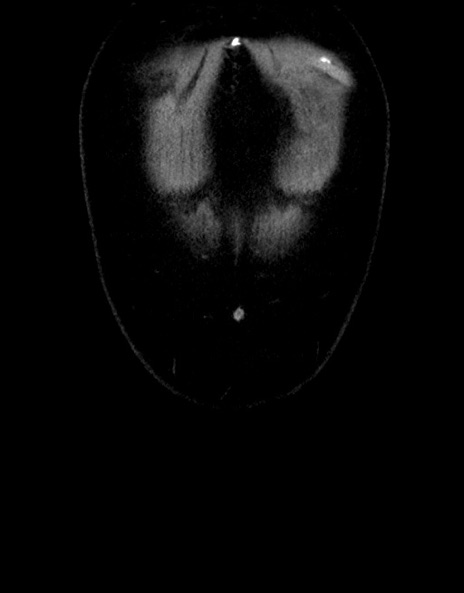

症例15(冠状断像)

症例

【症例】70歳代男性

【主訴】腹痛

【現病歴】今朝から腹痛あり。全体的に痛い。特に左上の方。排ガスが今日はない。冷や汗が出る。

【既往歴】直腸癌術後

【身体所見】左側腹部〜上腹部に圧痛あり。腹膜刺激症状明らかなではない。軽度反跳痛。左下腹部に術後瘢痕あり。

【データ】WBC 7700、CRP 0.02